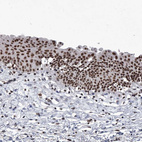

Immunohistochemical staining of human placenta shows strong nuclear positivity in trophoblastic cells.